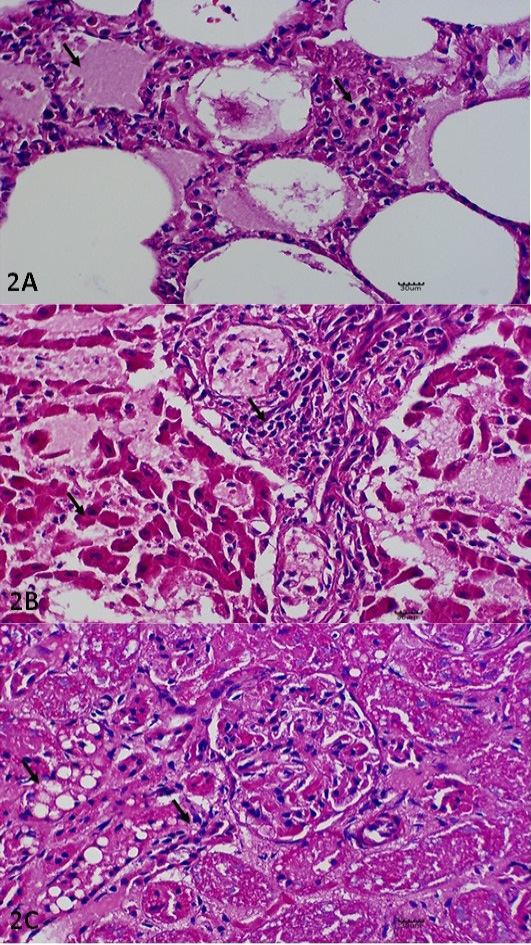

Histopathological Lesions. (A) Pulmonary edema and thickening of the interalveolar septae with leucocytic infiltration. H and E. X400. (B) Necrotising hepatitis, including necrotic changes on the hepatocytes with generalised infiltration of the leucocytes. H and E. X400. (C) Glomerular nephritis, including cytoplasmic vacuolation of the renal tubule (X) and epithelium clusters of scattered necrotic tubules (Y). H and E. X400. All the lesions described have been indicated in arrow (↘).